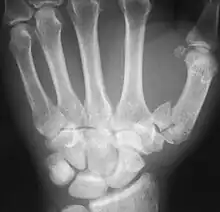

Fractures

Fractures to metacarpal bones account for 30-40% of all hand fractures, of which 25% occur in the first metacarpal (second to fractures to the fifth metacarpal bone). 80% of fractures to the first metacarpal occur at its base. [6]

Common fractures to the thumb metacarpal include Bennett's fracture and Rolando's fracture

Fracture of the first metacarpal (Rolando's fracture).- First metacarpal bone. Deep dissection.